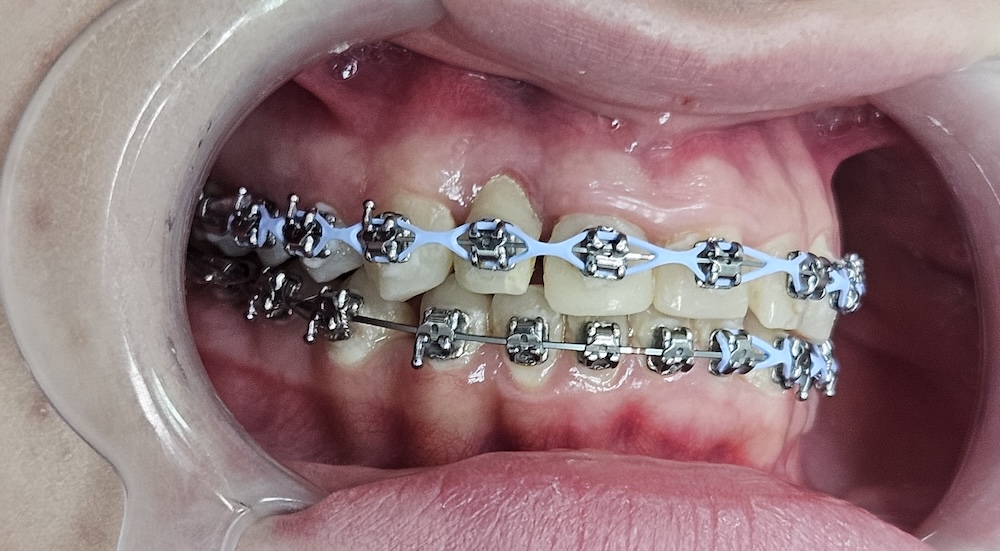

Вирівнювання зубів

Перед встановленням брекет-системи були видалені зуби мудрості. Це робиться не “про всяк випадок”, а для того, щоб звільнити місце і дати можливість зубам зайняти правильне положення без тиску ззаду. У цьому клінічному випадку перед брекетами видалили зуби мудрості, щоб створити місце для переміщення зубів і зменшити ризики ускладнень. Потребу в такому видаленні визначають індивідуально. В кінці 2023 року зафіксували металеву самолігуючу брекет-систему. Самолігуюча означає, що дуга фіксується без додаткових гумок — це дозволяє зменшити тертя і більш контрольовано переміщати зуби.